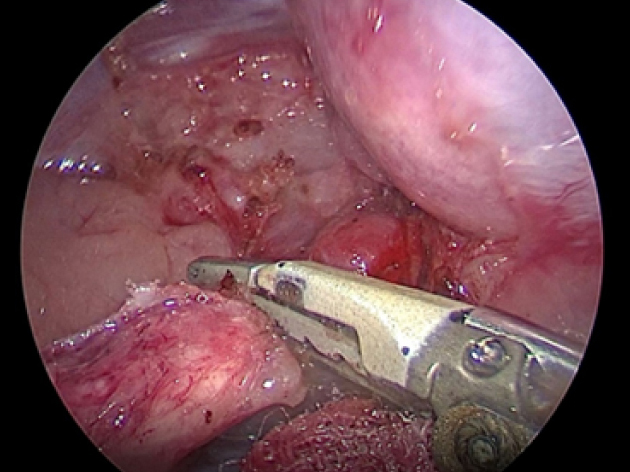

副腎の周りを完全に剥離したら超音波メスで離断していきます。

実際の手術風景です。